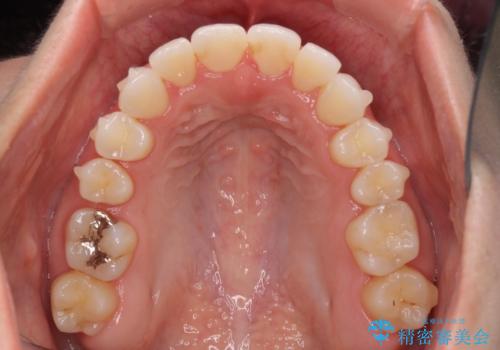

前歯のクロスバイトを治したい インビザラインによる矯正治療

- 前歯のデコボコとクロスバイトを治したいとのことで来院された患者様です。

上下顎ともに歯列全体の側方拡大とIPR(歯と歯の間を削る)によってデコボコとクロスバイトが解消するように設計し、インビザラインにより治療を行うこととしました。

下顎骨の左側への骨格的なずれが強く、上下の正中の位置合わせや奥歯の咬み合わせ構築に苦労しました。